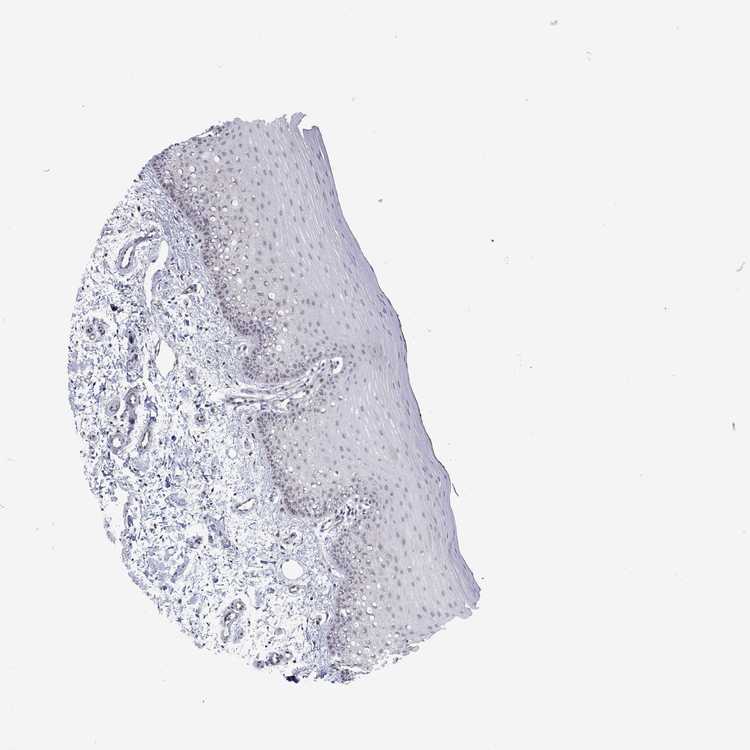

TISSUE PRIMARY DATA ORAL MUCOSA Show tissue menu

ORAL MUCOSA - Antibody stainingi

Antibody staining in the annotated cell types in the current human tissue is reported as not detected, low, medium, or high, based on conventional immunohistochemistry profiling in selected tissues. This score is based on the combination of the staining intensity and fraction of stained cells.

Each image is clickable and will lead to virtual microscopy that enables deeper exploration of all samples and also displays staining intensity scores, fraction scores and subcellular localization as well as patient and tissue information for each sample.

Antibody HPA022971Antibody HPA078575

Squamous epithelial cells Not detectedNot detected